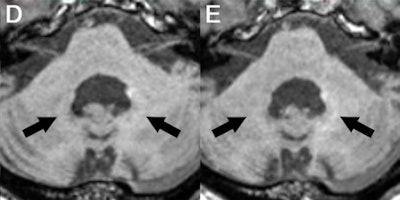

In the current retrospective study, Radbruch and colleagues narrowed their focus to possible evidence of signal intensity on unenhanced T1-weighted MR images in the dentate nucleus of patients who received an average of 23 injections of macrocyclic GBCAs.

Signal intensity ratio differences were calculated based on dentate nucleus-to-pons and dentate nucleus-to-middle cerebellar peduncle (MCP) values by subtracting the signal intensity ratio of the first MRI scan from the signal intensity ratio at the last MRI exam. The mean interval between the first and last MRI scans was 273 weeks.

The researchers found no significant T1 signal increase in the dentate nucleus in any of the patients after a mean 23 serial injections of the macrocyclic GBCAs. The findings were reinforced by the dentate nucleus-to-pons ratio of -0.0032 ± 0.0154 (p = 0.248) and the dentate nucleus-to-MCP ratio of -0.0011 ± 0.0093 (p = 0.521).